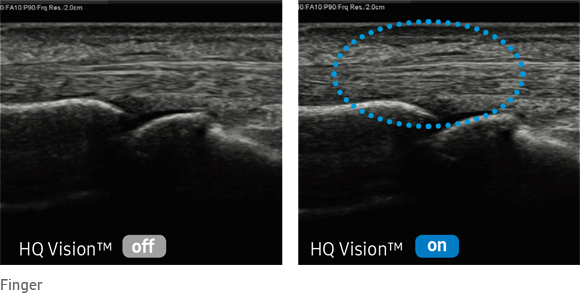

HQ Vision™

This new advanced technology is used to visualize anatomical structures. It helps you to make your diagnosis quickly and reliably.